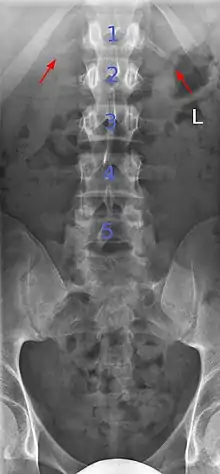

Lumbarization is an anomaly in the spine. It is defined by the nonfusion of the first and second segments of the sacrum. The lumbar spine subsequently appears to have six vertebrae or segments, not five. This sixth lumbar vertebra is known as a transitional vertebra. Conversely the sacrum appears to have only four segments instead of its designated five segments. Lumbosacral transitional vertebrae consist of the process of the last lumbar vertebra fusing with the first sacral segment. [1] While only around 10 percent of adults have a spinal abnormality due to genetics, a sixth lumbar vertebra is one of the more common abnormalities. [2]

Sacralization of the fifth lumbar vertebra (or sacralization) is a congenital anomaly, in which the transverse process of the last lumbar vertebra (L5) fuses to the sacrum on one side or both, or to ilium, or both. These anomalies are observed in about 3.5 percent of people, and it is usually bilateral but can be unilateral or incomplete (ipsilateral or contralateral rudimentary facets) as well. Although sacralization may be a cause of low back pain, it is asymptomatic in many cases (especially bilateral type). Low back pain in these cases most likely occurs due to biomechanics. In sacralization, the L5-S1 intervertebral disc may be thin and narrow. This abnormality is found by X-ray.

Sacralization of L6 means L6 attaches to S1 via a rudimentary joint. This L6-S1 joint creates additional motion, increasing the potential for motion-related stress and lower back pain/conditions. This condition can usually be treated without surgery, injecting steroid medication at the pseudoarticulation instead. Additionally, if L6 fuses to another vertebra this is increasingly likely to cause lower back pain. [3] The presence of a sixth vertebra in the space where five vertebrae normally reside also decreases the flexibility of the spine and increases the likelihood of injury. [4]